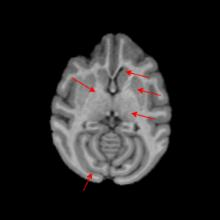

Non-human primates (NHPs) serve as critical models for understanding human brain function and neurological disorders due to their close evolutionary relationship with humans. Accurate brain tissue segmentation in NHPs is critical for understanding neurological disorders, but challenging due to the scarcity of annotated NHP brain MRI datasets, the small size of the NHP brain, the limited resolution of available imaging data and the anatomical differences between human and NHP brains. To address these challenges, we propose a novel approach utilizing STU-Net with transfer learning to leverage knowledge transferred from human brain MRI data to enhance segmentation accuracy in the NHP brain MRI, particularly when training data is limited. The combination of STU-Net and transfer learning effectively delineates complex tissue boundaries and captures fine anatomical details specific to NHP brains. Notably, our method demonstrated improvement in segmenting small subcortical structures such as putamen and thalamus that are challenging to resolve with limited spatial resolution and tissue contrast, and achieved DSC of over 0.88, IoU over 0.8 and HD95 under 7. This study introduces a robust method for multi-class brain tissue segmentation in NHPs, potentially accelerating research in evolutionary neuroscience and preclinical studies of neurological disorders relevant to human health.